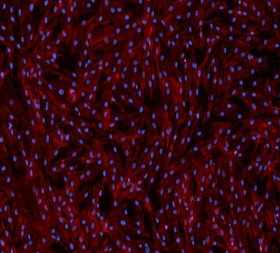

There are multiple characteristics of umbilical cord MSCs significantly superior to those derived from adipose, bone marrow or placental tissues. Umbilical cord MSCs have superior potency by mitochondrial and immunosuppression measurement and are the youngest adult stem cells, free from age related issues, prior medical conditions and genetics. AlloRx® Stem Cells are ethically sourced and derived from the Wharton’s Jelly of the umbilical cord. Strict screening of the donor’s medical & social history is evaluated as well as rigorous testing of the donor’s tissue is preformed prior to accepting cords.

Derived from the most potent stem cells measured by purity and potency, Wharton’s jelly of the umbilical cord, produced under strict quality control in a cGMP, ISO9001 & ISO13485 Certified environment. Our lead product candidate, AlloRx® has been used internationally to treat a variety of patients with autoimmune and inflammatory diseases, such as COPD, osteoarthritis, multiple sclerosis, Pitt-Hopkin’s, Alzheimer’s, and lupus.

Vitro Biopharma develops Wharton’s jelly of the umbilical cord-derived cell therapies to modulate the immune system and inflammation. Umbilical Cord MSCs are the youngest, most potent adult stem cells known, free from age related issues, prior medical conditions and genetics that come with use of adipose or bone-marrow-derived MSCs. UC-MSCs are significantly superior in multiple categories to other adult stem cells, including the ability to differentiate into neural stem cells (NSCs), adipose and bone-marrow-derived MSCs do not.

AlloRx® Stem Cells are derived from the Wharton’s Jelly of the umbilical cord. Cords are ethically sourced and donated after a baby is born. Strict screening of the donor’s medical & social history is evaluated as well as rigorous testing of the donor’s tissue is preformed prior to accepting cords. The cords are processed in Vitro Biopharma’s ISO 7 cleanroom with strict standard operating procedures and environmental controls. Through Vitro’s proprietary technology, we convert the cells into potential therapeutics by increasing the ATP expression, viability, yield, and has been seen to be more efficacious through different indications. We have a significant cost advantage within our manufacturing process which can derive trillions of cells from one umbilical cord.